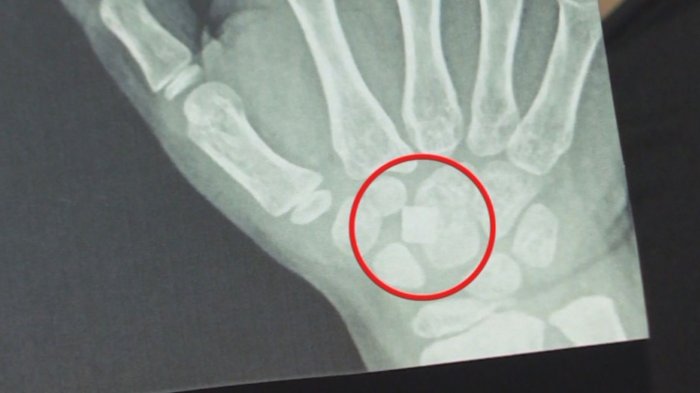

Denuncian negligencia médica: Niña vive hace tres meses con vidrio enterrado en su mano